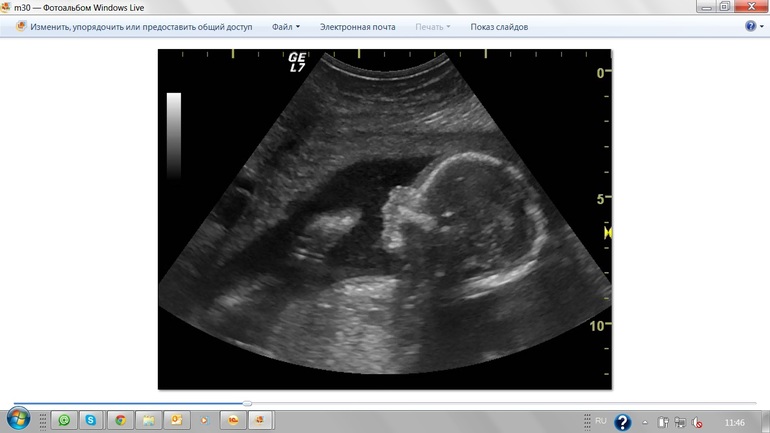

Мы даже под конец если честно устали немного!! Зато мы убедились что наш малыш в полном порядке, она в заключении даже не нашла что написать, ведь у малыша все развивается очень хорошо и точно по срокам)) А какой он энергичный!!! :) Даже муж обалдел! говорит, что не ожидал что он такой подвижный и так сильно тебя пинать!!

Сегодня сходили на скрининг первый раз. Врач сказала что ничего плохого у нас не нашла, только отклонение 5% в развитии носовой кости!!!Я в ужасе!!!У меня срок 12.3 а по УЗИ ставят 12.1! вот такие у нас размеры: КТР 57мм, Толщина воротникового пространства 1.1мм, а носовая кость 1.9мм!! На словах говорит что у болшинства здоровых детишек такие же отклонения бывают, но в заключении у меня написана: Гипоплазия НК :( Я сначала счастливая вышла из кабинета, а сейчас хоть плач!